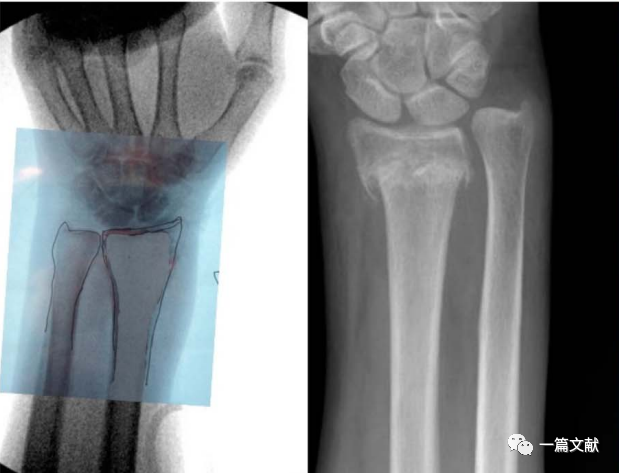

2、腕关节手术

虽然一般认为,术中恢复桡骨远端23°尺偏角,11°掌倾角,13mm的桡骨高度,即获得了良好的骨折复位。但是存在个体差异,例如尺骨变异患者。故此时,将患者健侧肢体作为参考对象最可靠。如下图:

左侧为健侧临摹图,右侧为骨折图

将此临摹图翻转后作为基准,进行骨折复位与固定